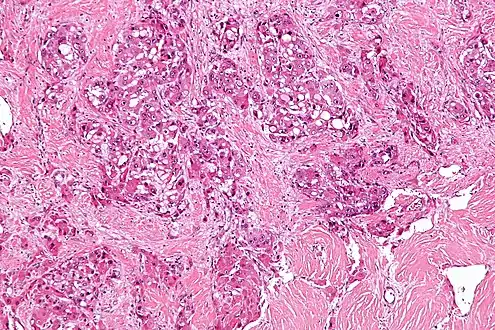

| Micrograph of fibrolamellar hepatocarcinoma showing the characteristic laminated fibrosis between the tumor cells with a low NC ratio. H&E stain. | |

The histopathology of FLC is characterized by laminated fibrous layers, interspersed between the tumor cells. Cytologically, the tumor cells have a low nuclear to cytoplasmic ratio with abundant eosinophilic cytoplasm.[1] Tumors are non-encapsulated, but well circumscribed, when compared to conventional HCC (which typically has an invasive border).

Intermed. mag.